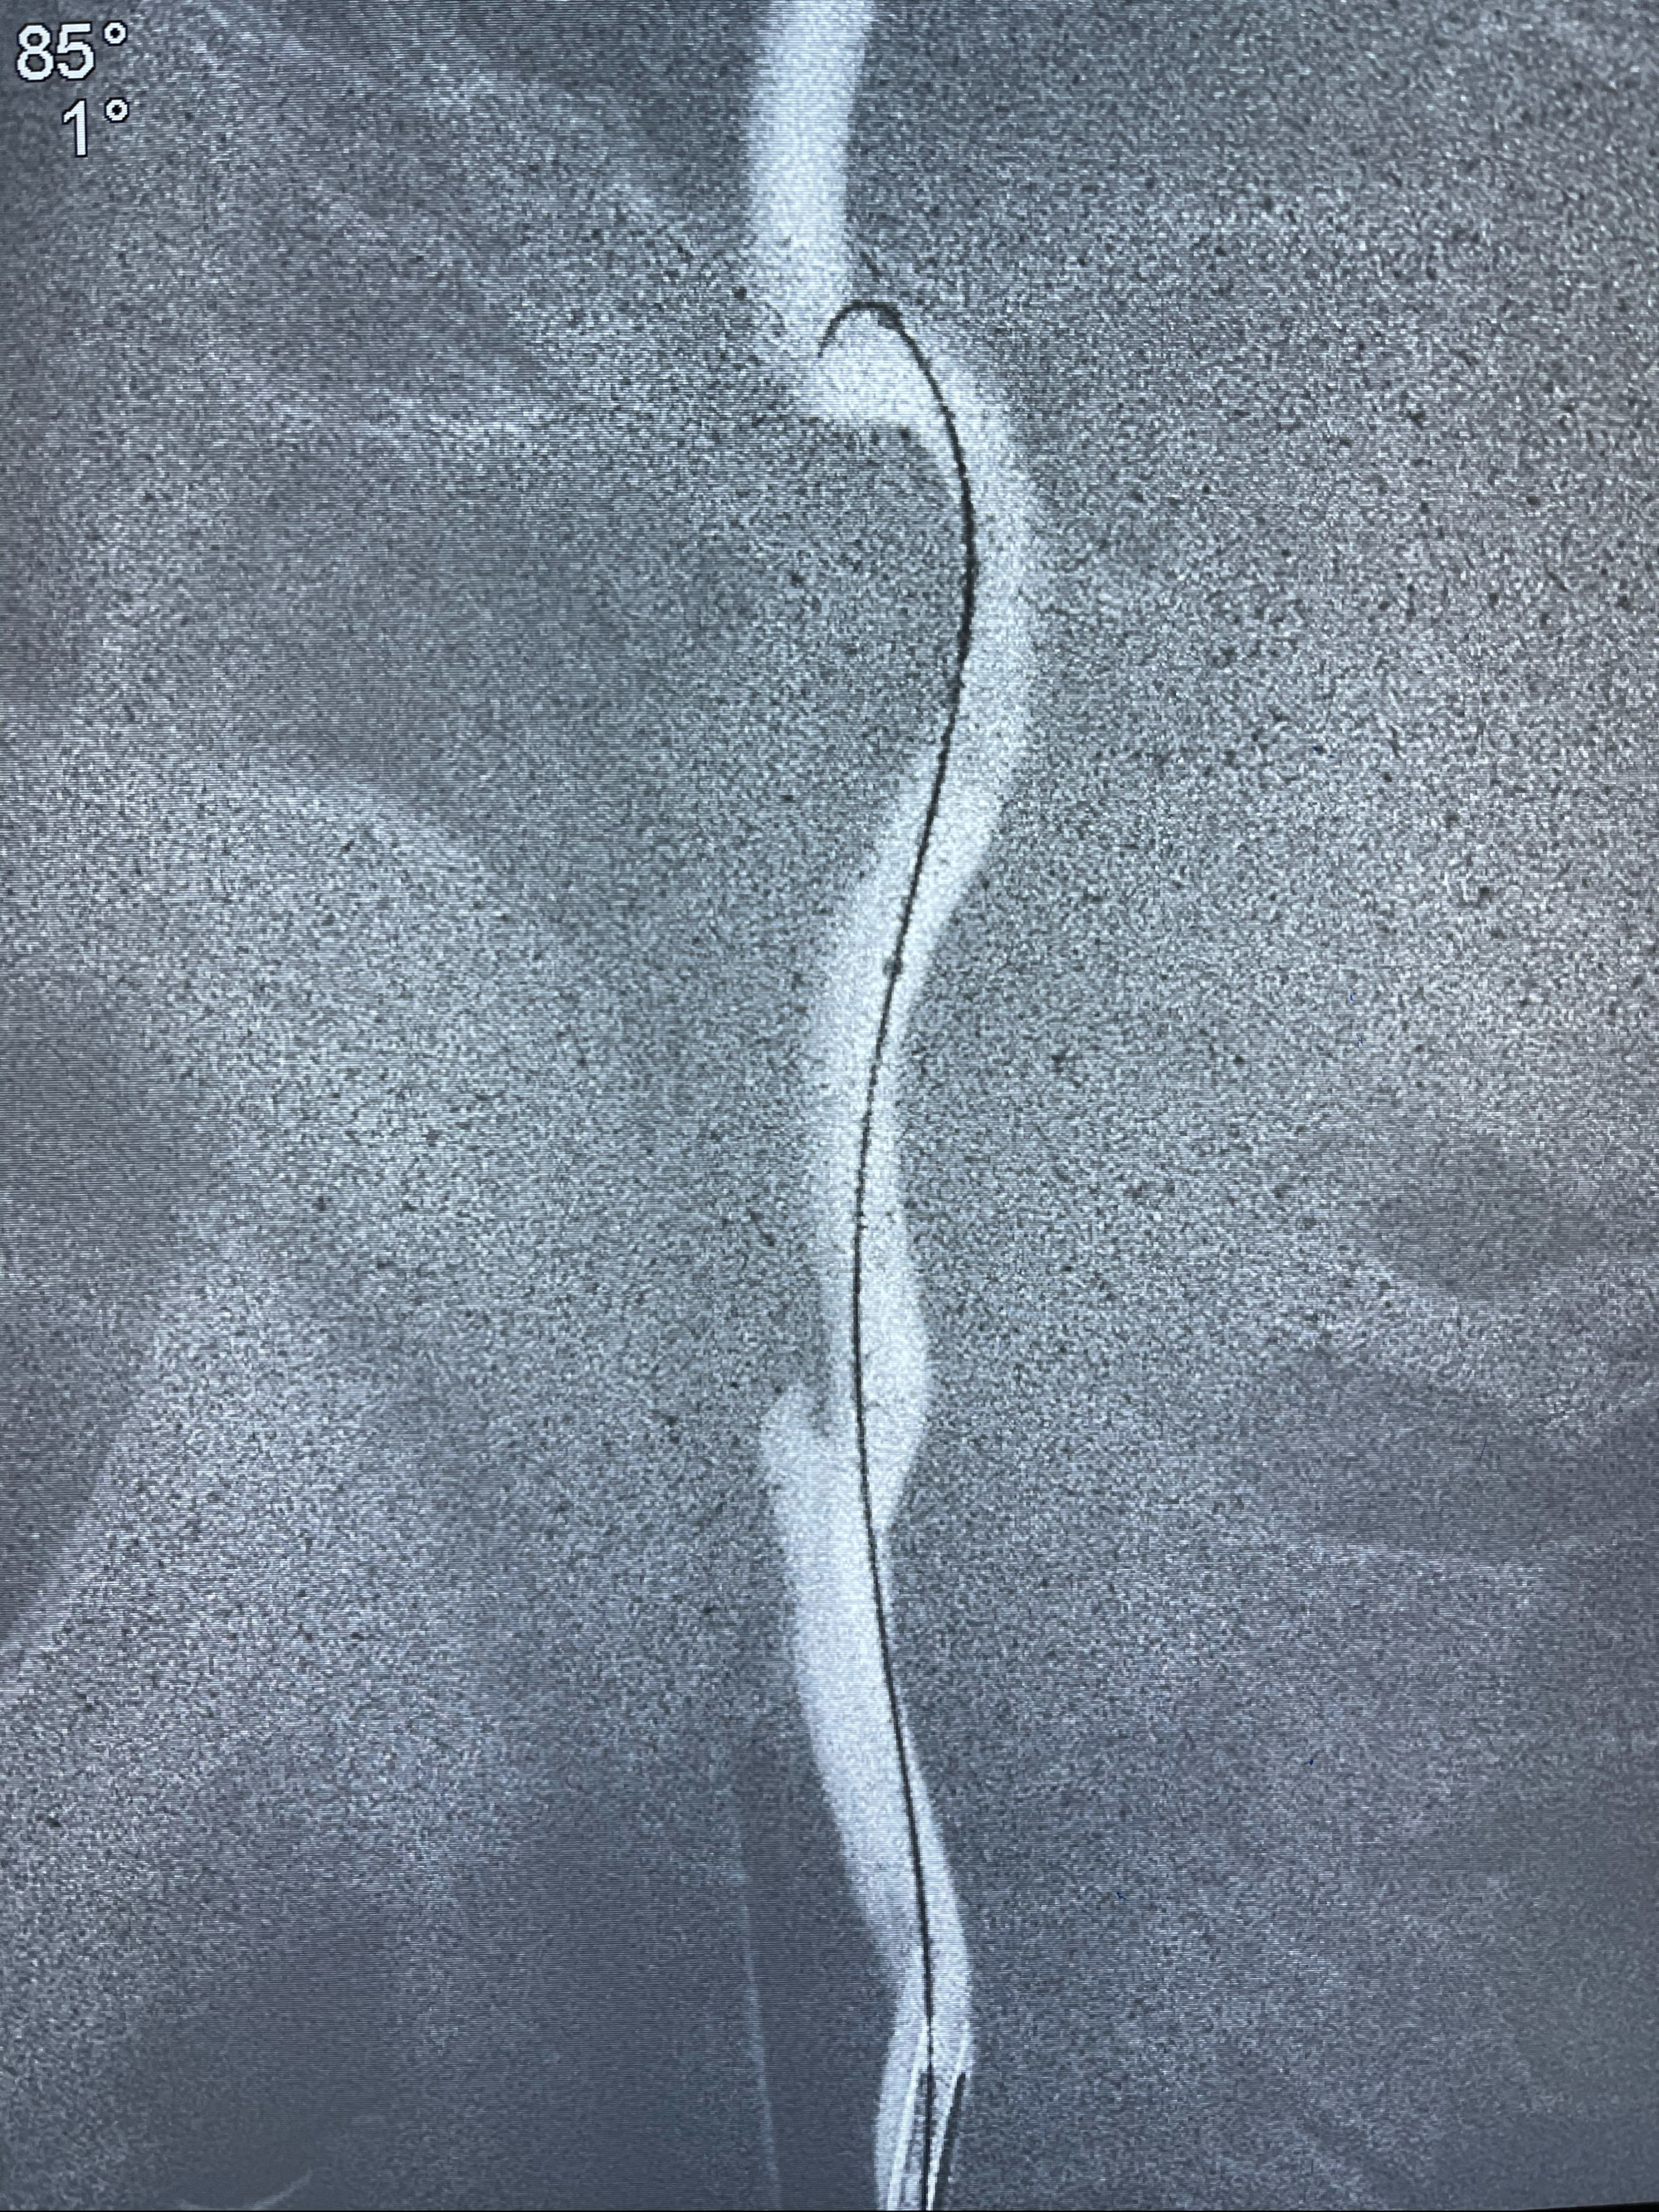

Eterprise4.0-23mm支架导管到位

Echelon10 45°角微导管塑形后到位

支架到位

支架释放,透视下